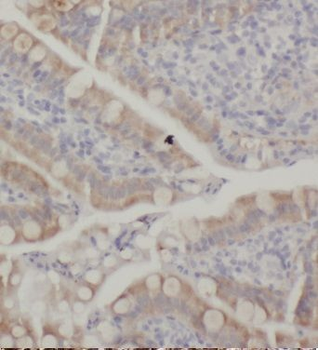

Immunohistochemistry of paraffin-embedded human small intestine tissue slide using orb628284 (KCNJ13 Antibody) at dilution of 1:50.